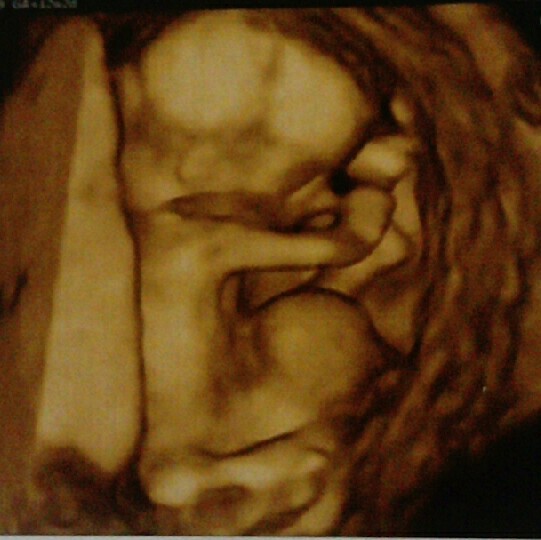

Nie było mnie bo dochodziłam do siebie po info z prenatalnych. Wstępne wyniki bez pappa to trisomia 13 1;10, trisomia 18 1;4, zespół downa 1;660. Kości nosowe słabo skostniałe, NT 1,6 - jedyne co jest wzorowe. Nadal ogromna przepuklina, która wszystko za sobą ciągnie, niżej jest serce, żołądek i przepona. Serduszko może w każdej chwili przestać bić bo nie ma warunków do prawidłowego wzrostu. Byłam u 4 lekarzy i każdy mówi to samo. W 9 tyg była nadzieja, że to się wchłonie ale teraz pozostaje modlić się żeby moja mała córeczka jak najkrócej cierpiała. Mam czekać do kolejnej wizyty 17,09 i albo amnio albo na wywołanie poronienia. Kolejna moja ciążą to raczej będzie z in vitro bo chce uniknąć wad genetycznych. Dowiedziałam się, jajeczko jest badane pod tym kątem przed i po podziałach komórkowych. To jest dla mnie jedyne rozwiązanie.

Załączniki

• _20200907_163945.JPG

_20200907_163945.JPG

55,8 KB · Wyświetleń: 135